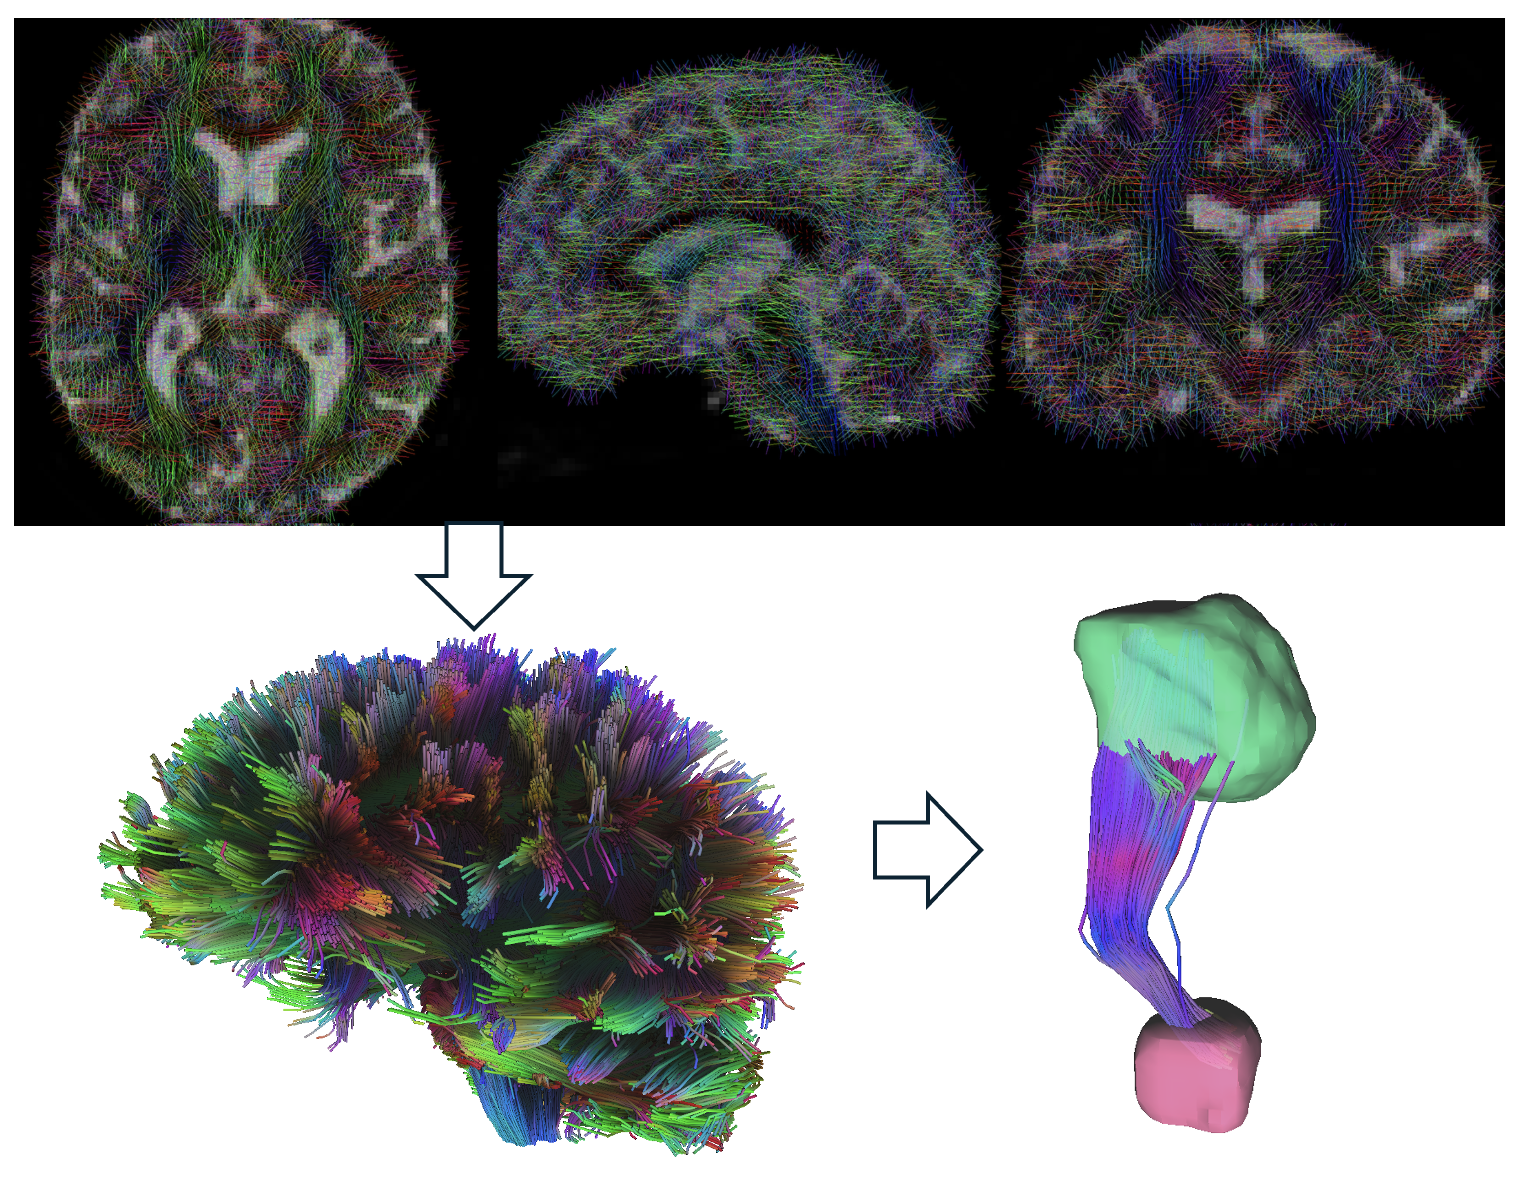

Method: Patient-specific tractography was performed in nine PD patients using preoperative 3T MRI. Tractography processing included motion artifact correction via QSIRecon and visualization in DSI Studio with native space alignment using patient-specific T1 imaging. SMA and preSMA regions were extracted from the HMAT atlas and transformed into native space, while VTA was reconstructed using Lead-DBS based on stimulation parameters three months postoperatively (SimBio model). No further changes in stimulation settings or medication were made before the six-month follow-up. Connectivity between VTA and SMA/preSMA was quantified, and correlation analyses were conducted with changes in TUG and STS test results, defined as the difference between preoperative (Med ON) and six-month postoperative (DBS ON, Med ON) assessments.

Pipeline of patient-specific tractography.